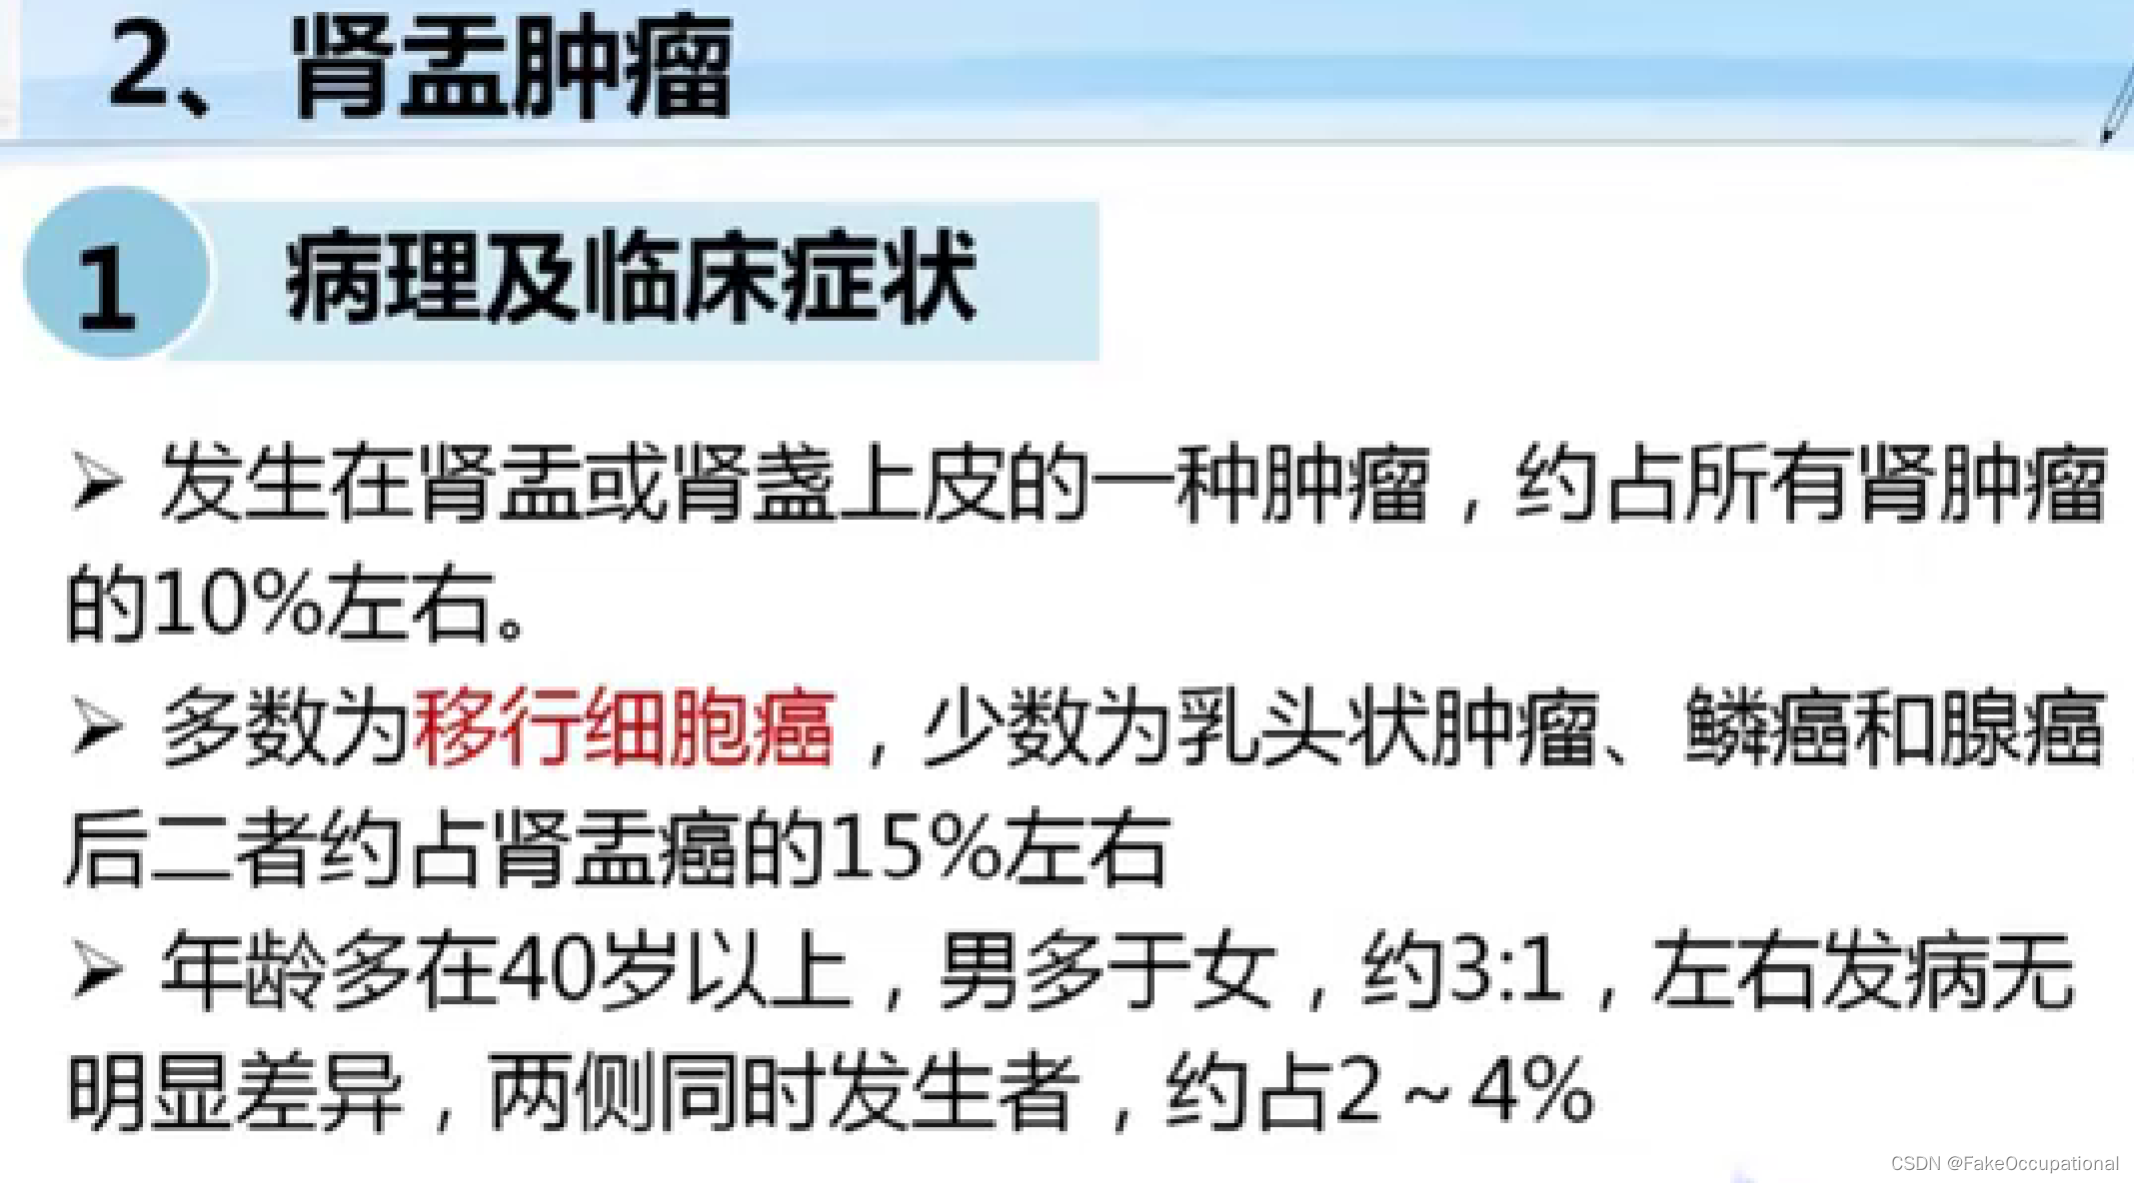

- 掌握肾脏、输尿管膀胱及前列腺疾病的超声诊断要点.1超声表现。熟悉泌尿系统的正常检查技术。了解泌尿系统的超声

- 重点内容:泌尿系的常见疾病

- 难点内容:泌尿系疾病的肿瘤,尤其是恶性肿瘤。